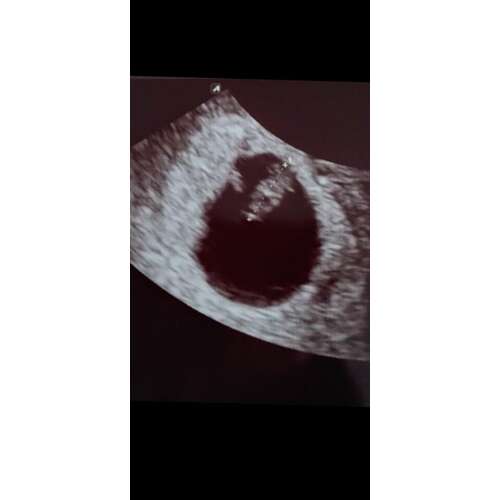

dit was bij mij met 8 weken, zie je ook niet erg veel in nog als je het mij vraagt

dit was bij mij met 8 weken, zie je ook niet erg veel in nog als je het mij ...